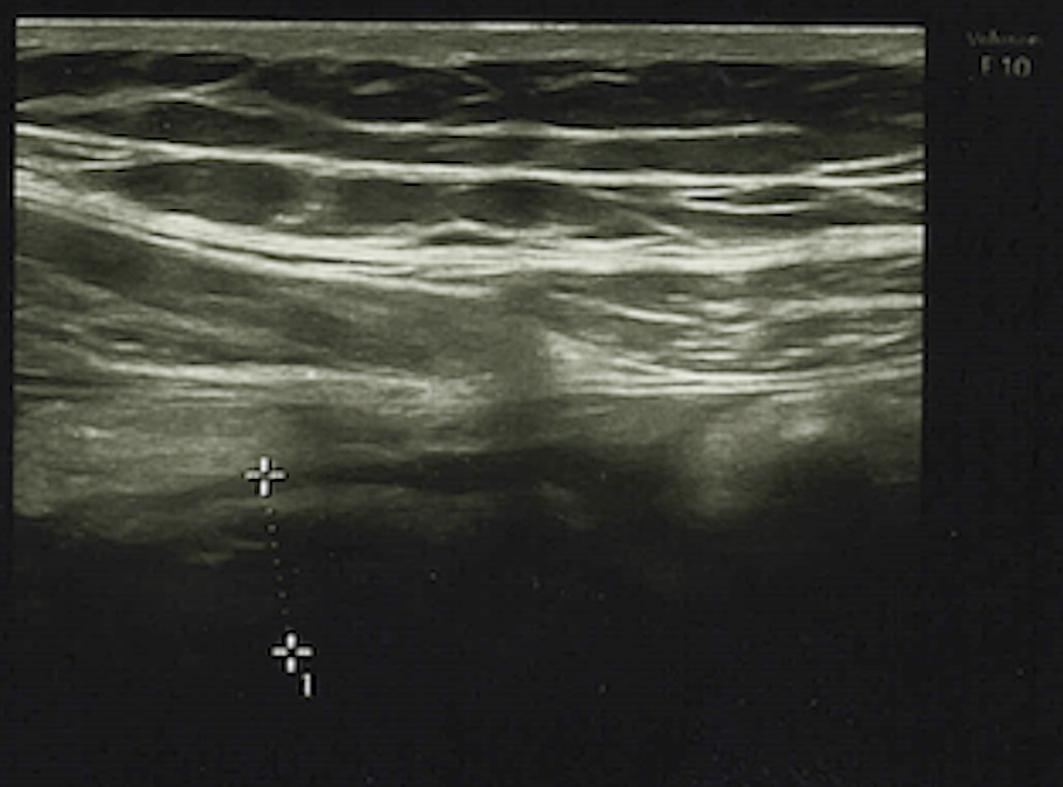

腹部超声检查显示回盲隐窝积液,阑尾直径10mm并伴有阑尾周围炎症,提示急性阑尾炎(图1)。

(图1 超声检查)